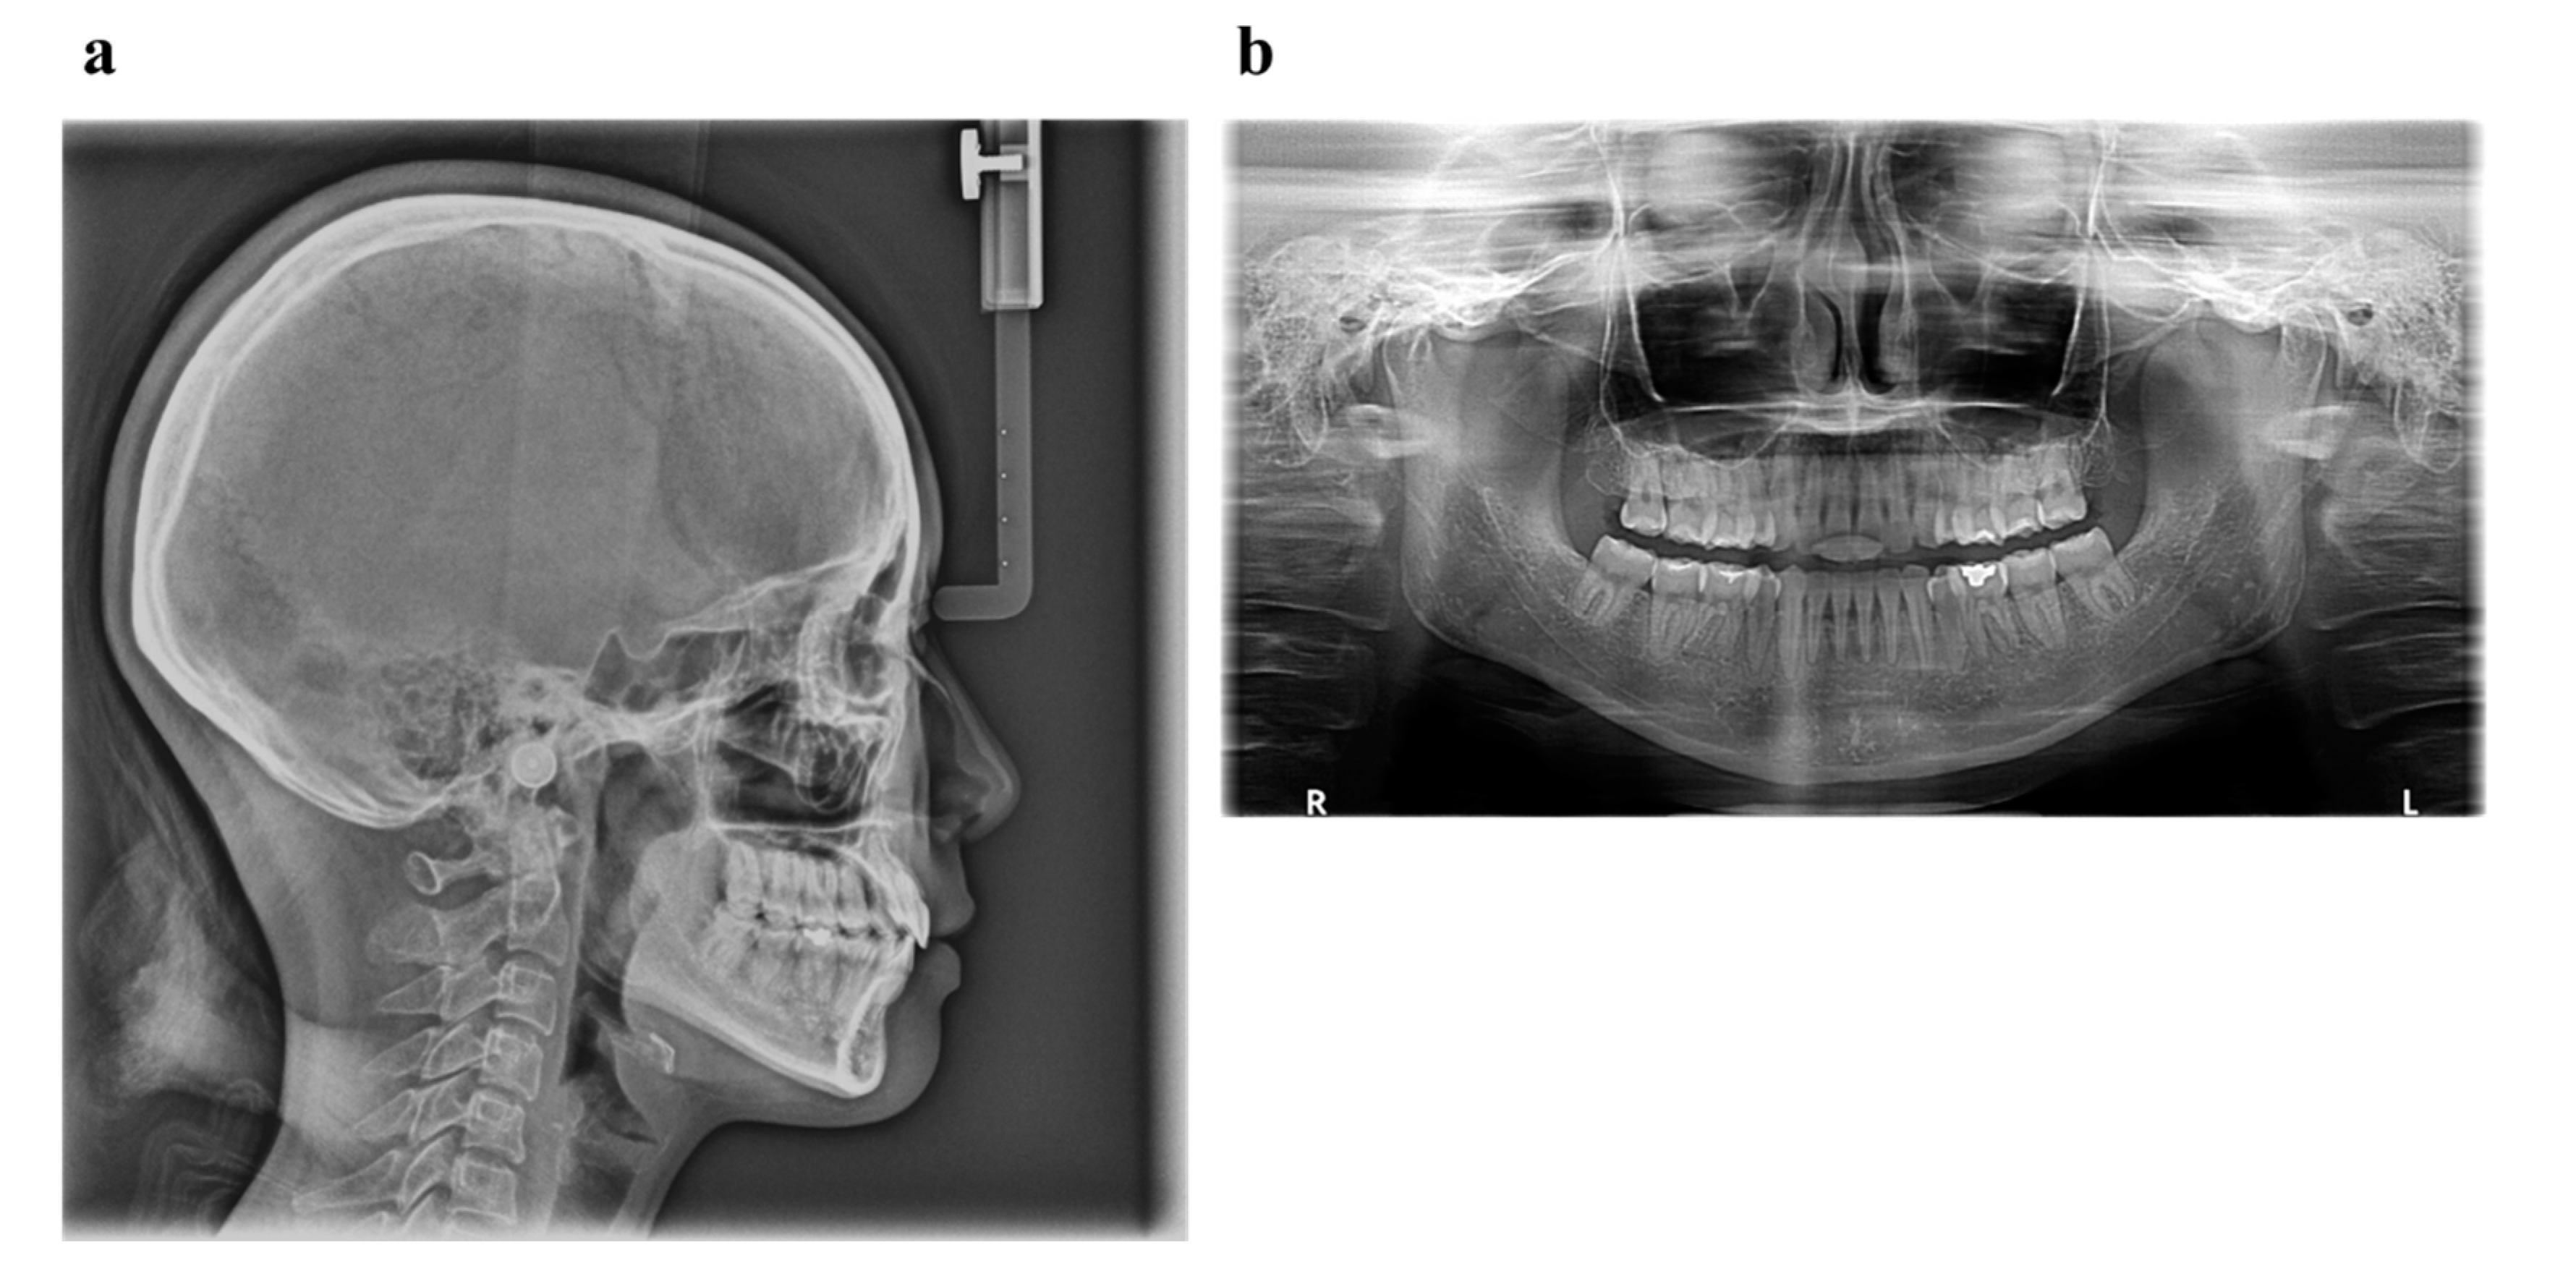

| Measurement | Normal (Japanese Woman) | Pretreatment (29 y 19 m) | Posttreatment (31y 2m) |

|---|---|---|---|

| SNA (° ) | 81.3 ± 2.7 | 80.0 | 80.0 |

| SNB (° ) | 78.6 ± 2.7 | 79.5 | 79.0 |

| ANB (° ) | 2.6 ± 1.1 | 0.5 | 1.0 |

| FMA (° ) | 26.3 ± 4.1 | 24.0 | 24.0 |

| FMIA (° ) | 56.9 ± 6.4 | 52.0 | 61.0 |

| IMPA (° ) | 96.8 ± 6.4 | 104.0 | 95.0 |

| U1-FH (° ) | 112.1 ± 4.2 | 126.5 | 115.5 |

| U1-L1 (° ) | 123.5 ± 5.5 | 105.0 | 125.0 |

| U1-A-Pog (mm) | 6.2 ± 1.5 | 11.2 | 4.6 |

| L1-A-Pog (mm) | 3.0 ± 1.5 | 8.1 | 2.3 |

| Gonial angle (° ) | 118.8 ± 6.1 | 117.5 | 117.5 |

| E-line: Upper (mm) | 1.4 ± 2.0 | −0.5 | −2.0 |

| E-line: Lower (mm) | 1.4 ± 2.0 | +0.3 | −0.7 |